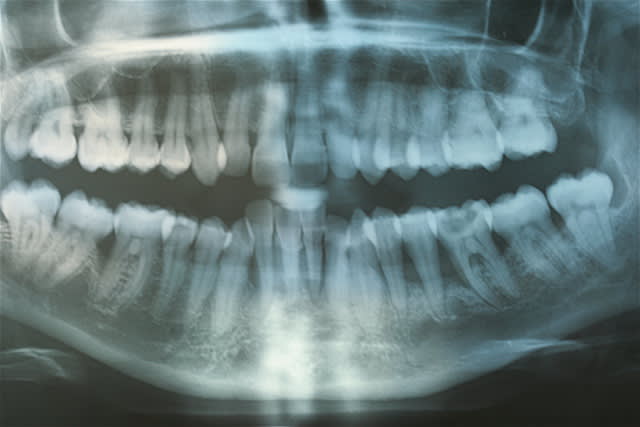

je peux vous soumettre quelques clichés, je crois intéressants ...j'ai investit dans du matériel photo pour vous séduire, acheté des habits sérieux...

toujours aucune extractions depuis 8 ans, sur des cas de paro nommé irréparable par les plus grands parodontistes de France et de suisse! LOL

lus de 250 cas extrêmes et difficiles traités prouvent que nous sommes bien en présence d'une blessure souillée et qu'il suffit de la traiter comme toute blessure souillée.

Montre nous des cas bien présentés (radio, rétro, sondage, photo de qualité)

Les photos que tu montres ne donnent aucun renseignement quand à la guérison du parodonte (Ah oui , pardon ce n'est pas une maladie ).